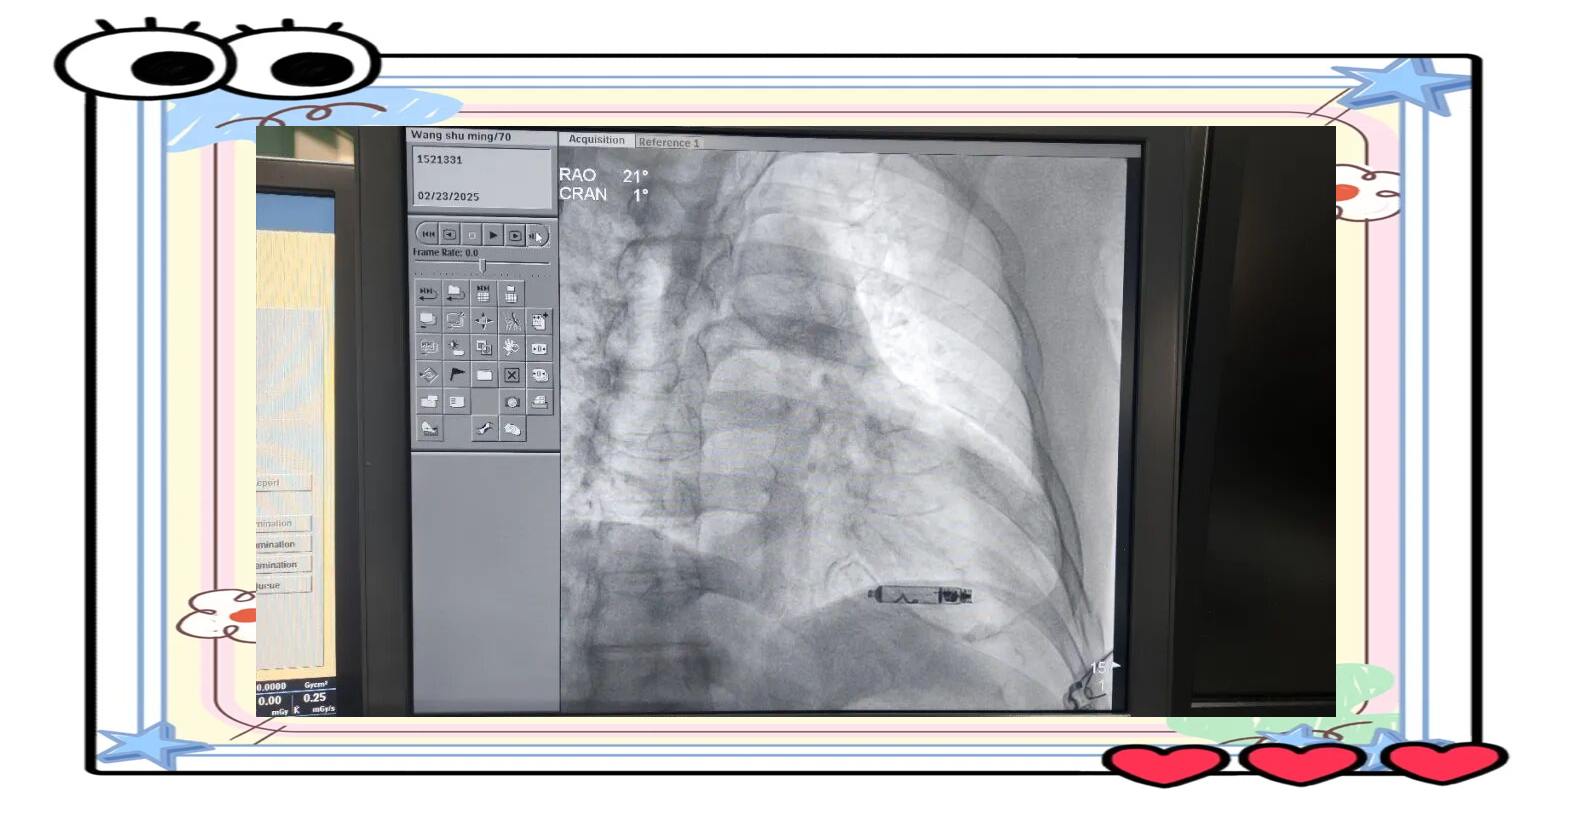

图片来源于网络,如有侵权,请联系删除